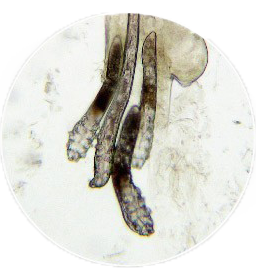

ㆍ頭髮檢查:

用來檢查頭髮外觀是否有異常,及

是否受到黴菌感染。